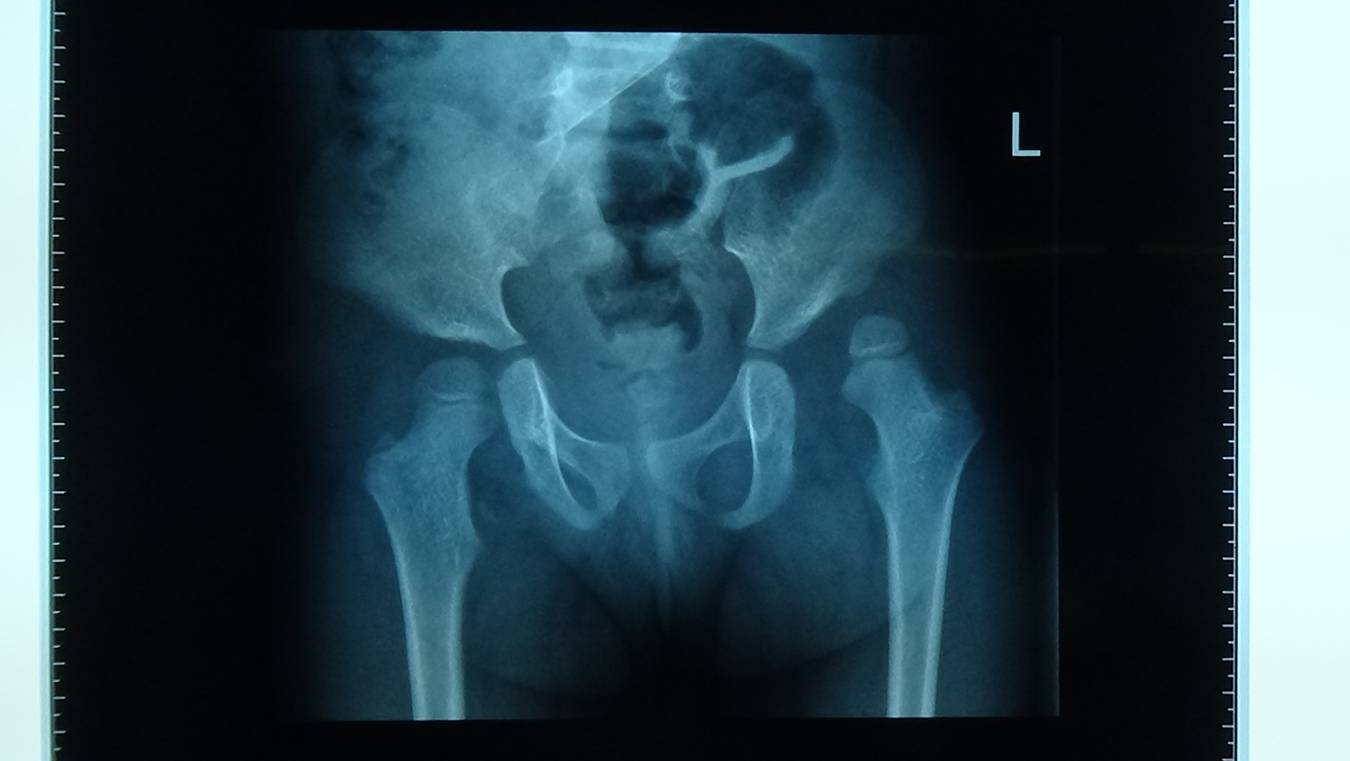

2、X线检查

X线检查可发现正常髋臼顶壁的骨化延迟。其原因是健康人髋臼内收位时股骨头压力降低,作用于髋臼中心。外展型挛缩如不尽早纠正,可导致健康的髋关节半脱位。X线检查还可排除某些导致骨盆倾斜的畸形,例如腰骶半椎体,先天性脊柱侧弯等。